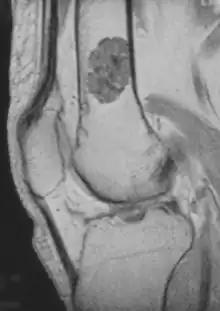

MRI T1 showing an enchondroma in the femur.